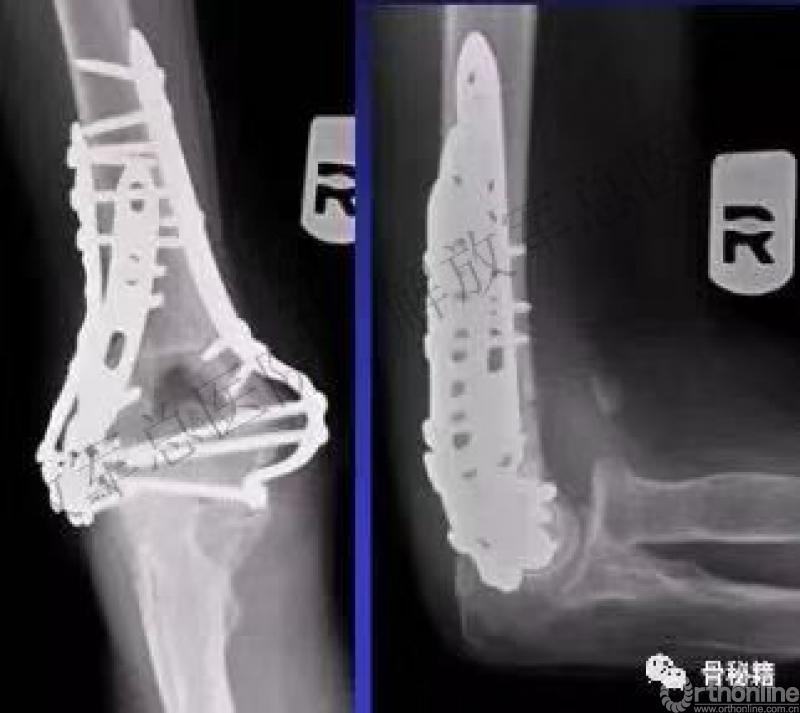

四、适当的固定技术原则

1.最大限度地固定远端碎片。

2.确保远端节段的所有固定有助于提高髁间水平的稳定性。

3.不建议使用三分之一管型板,因为它们太弱并易于断裂,尤其是在粉碎干骺端。

4.钢板长度也很重要:钢板应在近端以不同水平,以避免在肱骨干骨中形成应力集中。

5.解剖锁定钢板通过卓越的生物力学特性提供更好的临床疗效。

6.良好的固定需要两个板,平行or垂直?

在肱骨远端骨折中,一块钢板通常不足以保证良好的稳定性,而在其他骨折(例如,胫骨近端和股骨远端)中,LCP的引入消除了对双柱固定的需要。应谨慎使用单侧钢板,仅在单柱损伤的情况下可以应用。

7.钢板如何搭配?

迄今为止,通常使用前两种钢板的固定。

AO推荐在治疗中应用垂直钢板。然而,这种方法受到了广泛的批评 - 主要是因为通过后外侧板难以获得足够的螺钉数量和前后方向的长度的螺钉固定。

与垂直钢板相比,平行板配置似乎提供了更好的生物力学性能。实在不行的时候再用三钢板技术

五、固定的八个细节

1.每个螺钉都应该经过钢板固定。

2.每个螺钉固定骨折块的螺钉,在他的对侧应该也有一个钢板的把持。

3.在远端一定要打满螺钉。

4.每个螺钉要尽可能的长。

5.每个螺钉需要尽量的对关节面的骨块进行固定。

6.螺钉应通过交叉锁定在一起,从而形成角稳定结构并将内外侧柱连接在一起。

7.钢板需要在髁间完成加压。

8.所使用的钢板必须足够坚固并且足够坚硬以抵抗在髁上水平处的断裂或弯曲。